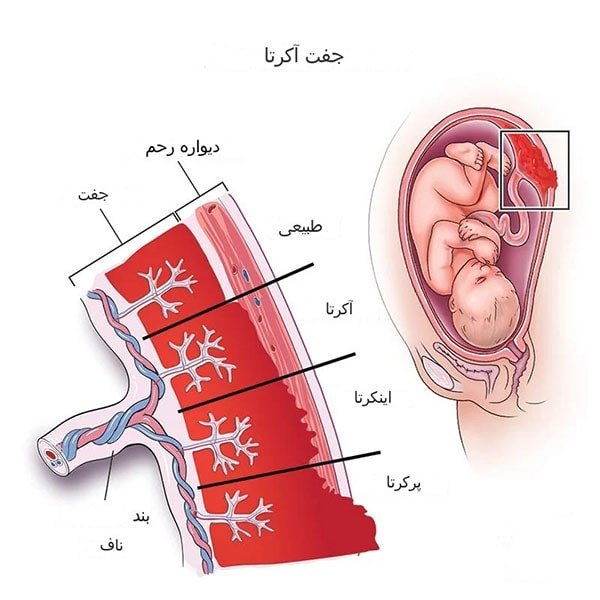

-جفت آکرتا: هنگامی که جفت (یا بخشی از جفت) به دیواره رحم حمله می کند و از دیواره رحم جدا نمی شود، جفت آکرتا نامیده می شود. جفت آکرتا می تواند باعث خونریزی در سه ماهه سوم و از دست دادن خون شدید در هنگام زایمان شود. اکثر موارد را می توان در دوران بارداری با انجام معمول سونوگرافی پیدا کرد. با این حال، گاهی اوقات تا پس از تولد نوزاد کشف نمی شود. اگر جفت آکرتا دارید، در معرض خطر از دست دادن خون در حین زایمان هستید. پزشک زایمان شما را با دقت برنامه ریزی می کند و مطمئن می شود که همه منابع مورد نیاز در دسترس هستند. ممکن است لازم باشد نوزاد خود را در بیمارستانی که در این عارضه تخصص دارد به دنیا بیاورید. گاهی با توجه به وسعت چسبندگی جفت، هیسترکتومی یعنی خروج رحم باید بلافاصله پس از زایمان انجام شود تا با متوقف کردن خونریزی از تهدید به مرگ جان مادر جلوگیری شود.

جفت آکرتا: وضعیتی که در آن بخشی یا تمام جفت به طور غیر طبیعی به رحم می چسبد.